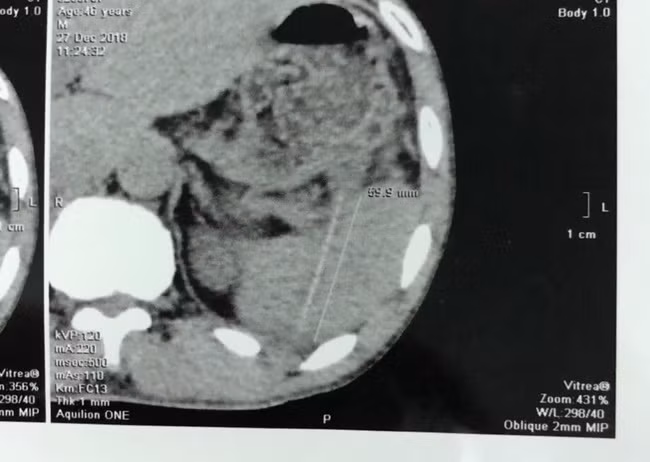

Trước đó, đau vùng hạ sườn trái suốt 2 tuần mà không rõ nguyên nhân, anh H. đến Trung tâm chẩn đoán Y khoa MEDIC tại TPHCM để thăm khám. Tại đây, các bác sĩ phát hiện dị vật có hình dạng một cây tăm nằm trong nhu mô lách, một đầu cắm vào rốn lách, nguy cơ sẽ xuyên thủng động mạch lách.

| Hình chụp CT scaner thấy cây tăm trong ổ bụng bệnh nhân. Ảnh BVCC |